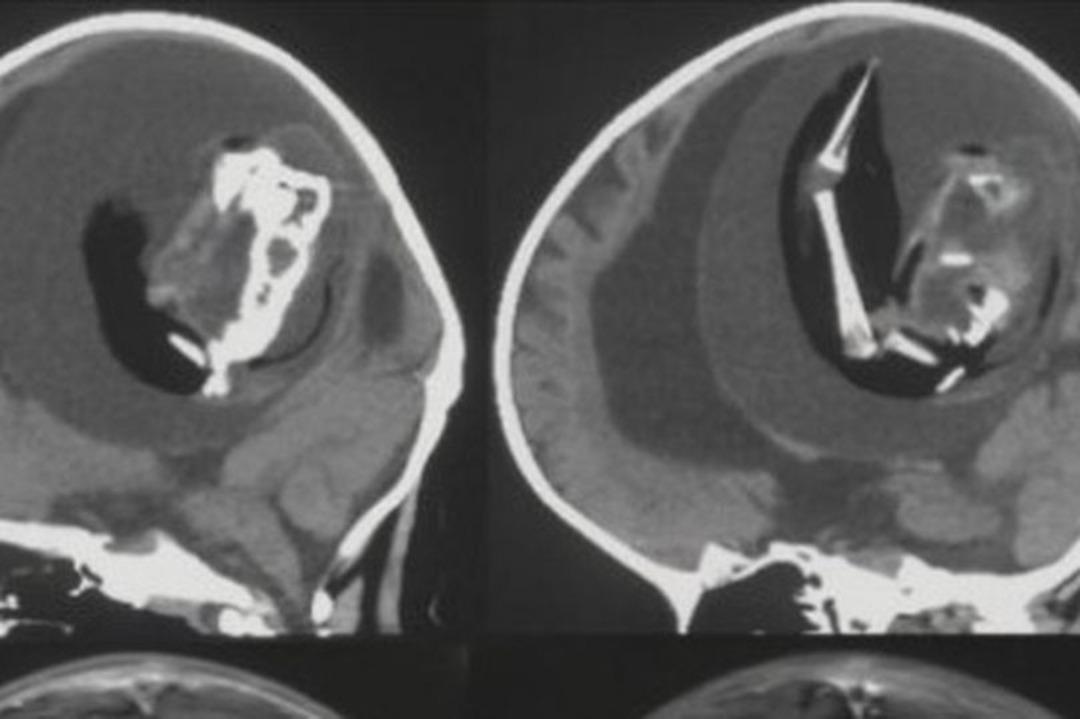

Çin’deki Feudan Üniversitesi’nde ilginç bir tıbbi vaka yaşandı. İsmi açıklanmayan 1 yaşındaki kız çocuğunun doğmamış ikizinin anne karnındayken kafasının içine girerek büyümeye devam ettiği belirlendi. Fetüs içinde fetüs olarak bilinen bu tıbbi durumda 1 yaşındaki kız çocuğunun kafasının içindeki ikizinin fetüsü büyümeye devam etti. Fetüsün üst uzuvları, kemikleri ve tırnakları gelişti. Durum BT taramalarında tespit edildi.

Kızın doğumundan yaklaşık 1 yıl boyunca fark edilmeyen fetüs hayatta kalan ikizi ebeveynlerinin büyük kafatası ve motor becerilerindeki problemler nedeniyle hastaneye götürmesiyle ortaya çıktı. Fetüs, kardeşiyle kan akışını paylaştığı için kafatasının içinde bir yıl hayatta kalmayı başardı, ancak sonunda ameliyatla alındı.

Kızı tedavi eden bir nörolog olan Dr. Zongze Li, “İntrakraniyal ceninin, ayrılmamış blastosistlerden kaynaklanıyor.Yapışkan parçalar, konakçı fetüsün ön beynine dönüşür ve nöral plaka katlanması sırasında diğer embriyoyu sarar” dedi.